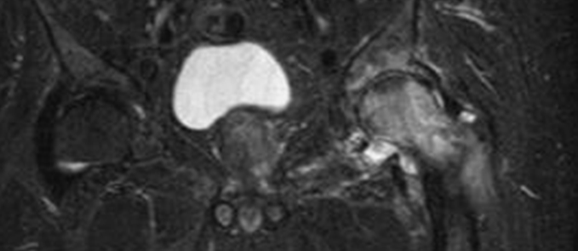

En RM hay aumento del liquido articular que distiende la cápsula, hiperintenso en T2. (Fig 53 A). El líquido infectado y/o con hemartrosis, tiene una señal intermedia y heterogénea. (20).

B: RM coronal y C: RM axial en STIR. Se confirma el derrame articular, por artritis infecciosa.

B: RM coronal y C: RM axial en STIR. Derrame articular, por artritis infecciosa. En B hay cambios inflamatorios en la cavidad acetabular y en C en los músculos vecinos.

RM coronal en STIR. Disminución del espacio articular, con cambios inflamatorios en la cavidad acetabular y la cabeza femoral por artritis.